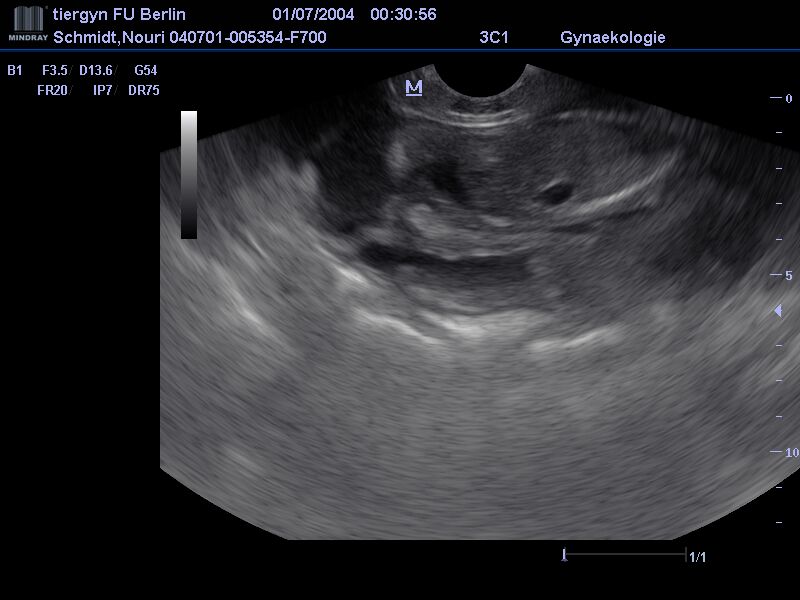

Dies ist der beste Zeitpunkt, um die Trächtigkeit anhand des Herzschlags zu diagnostizieren. Die Embroynen sind etwa walnussgroß und sind gleichmäßig im Uterus verteilt. | ![]() |

==> 15.09.2023: Nun haben wir es sozusagen "Weiß auf Schwarz"....Nouri ist trächtig!!!! Auf dem Ultraschall waren 7 - 8 Embryonen zu sehen. Falls alles ohne Resorptionen oder Komplikationen verläuft, erwarten wir somit einen größeren Wurf. |

Man konnte sogar schon einige kleine Herzchen schlagen sehen - ein bewegender Moment. Laut Vermessung der Fruchtblasen sind wir heute am 23. Trächtigkeitstag. Das heißt, dass die Befruchtung am 2. Deckungstag stattgefunden hat (22.08.2023). |